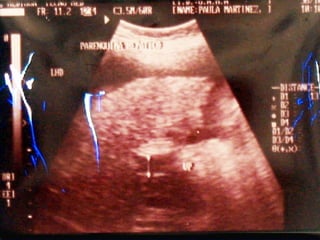

SONOGRAMA ABDOMINAL EVALUACIÓN HIGADO SISTEMA BILIAR BAZO  RIÑONES PANCREAS ( no específico)

SONOGRAMA ABDOMINAL EVALUACIÓN HIPERTENSIÓN PORTAL : Aumento del diámetro de la porta (vena mesentérica y esplénica) aumento de calibre que no cambia con la respiración. Esplenomegalia Ascitis

SONOGRAMA ABDOMINAL EVALUACIÓN TAMAÑO ( Hepatitis, I.C.C., Cirosis) FORMA (lobular en cirrosis) LOCALIZACIÓN ( de masas) PATRON SONOGRÁFICO ( hiperecoico gris)